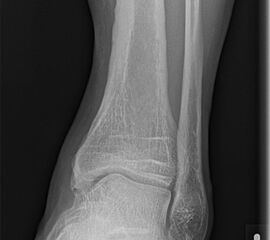

Röntgen

Die Standard Röntgendiagnostik des Sprunggelenks umfasst Bilder in anteriorposterioren (a.p.) und im seitlichen Strahlengang 6. Für die exakte Abbildung des Innenknöchels müssen beide Malleolen parallel zur Röntgenplatte zu liegen kommen. Je nach Torsion der Tibia macht dies eine Innenrotation des Fußes zwischen 10° und 30° erforderlich (Abb. 3).

Manchmal sind mediale Malleolarfrakturen nur in einer der Aufnahmen in ihrem Ausmaß erkennbar. Keine Rolle spielt die gehaltene Aufnahme beim Kind, insbesondere bei der akuten Verletzung. In seltenen Fällen hat dieses Verfahren bei Verdacht auf eine chronische Instabilität eine Berechtigung.

Fugengelenkfrakturen treten typischerweise vor dem 10. Lebensjahr auf, in einer Phase, in welcher die Wachstumsfugen noch weit offen sind. Dieser Frakturtyp betrifft fast ausschließlich den medialen Malleolus. Laterale Frakturen sind extrem selten, teilweise kommt es zu lateralen Bandverletzungen oder Fugenschaftfrakturen der distalen Fibula. Die Frakturlinie verläuft in einer Verlängerungslinie von der medialen Taluskante nach proximal. Häufig stellen sich Verletzungen des Innenknöchels im Röntgenbild schlechter dar, insbesondere wenn die Aufnahmen verdreht sind oder die Ebene der Fraktur bei geringer Dislokation verkippt zur Röntgenebene liegt. Besteht klinisch der geringste Hinweis auf eine Verletzung des Innenknöchels, muss aufgrund der Tragweite der Verletzung durch entsprechende Aufnahmen gegebenenfalls auch Schnittbildverfahren die Verletzung sicher diagnostiziert oder ausgeschlossen werden (Abb. 15).